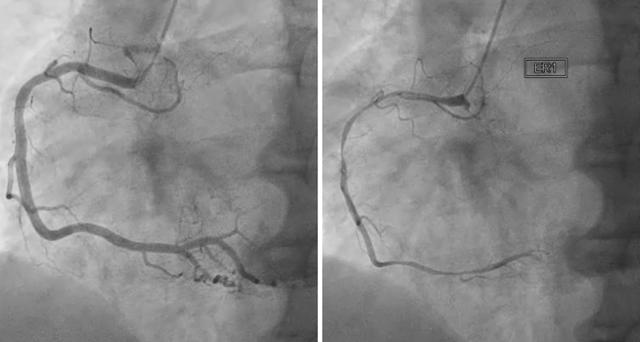

협심증은 심장에 혈액이 충분히 공급되지 못하여 가슴 통증이 발생하는 질환을 의미합니다. 협심증의 원인은 주로 심장의 동맥인 관상동맥이 좁아지거나 막히기 때문입니다. 관상동맥은 심장에 혈액을 공급하는 동맥으로, 이 동맥이 좁아지거나 막히면 심장에 충분한 혈액이 공급되지 못하여 가슴 통증이 발생합니다.

동맥경화: 동맥경화는 동맥 내부에 콜레스테롤, 지방, 혈전 등이 쌓여 동맥이 좁아지는 질환입니다. 동맥경화는 협심증의 가장 흔한 원인입니다.